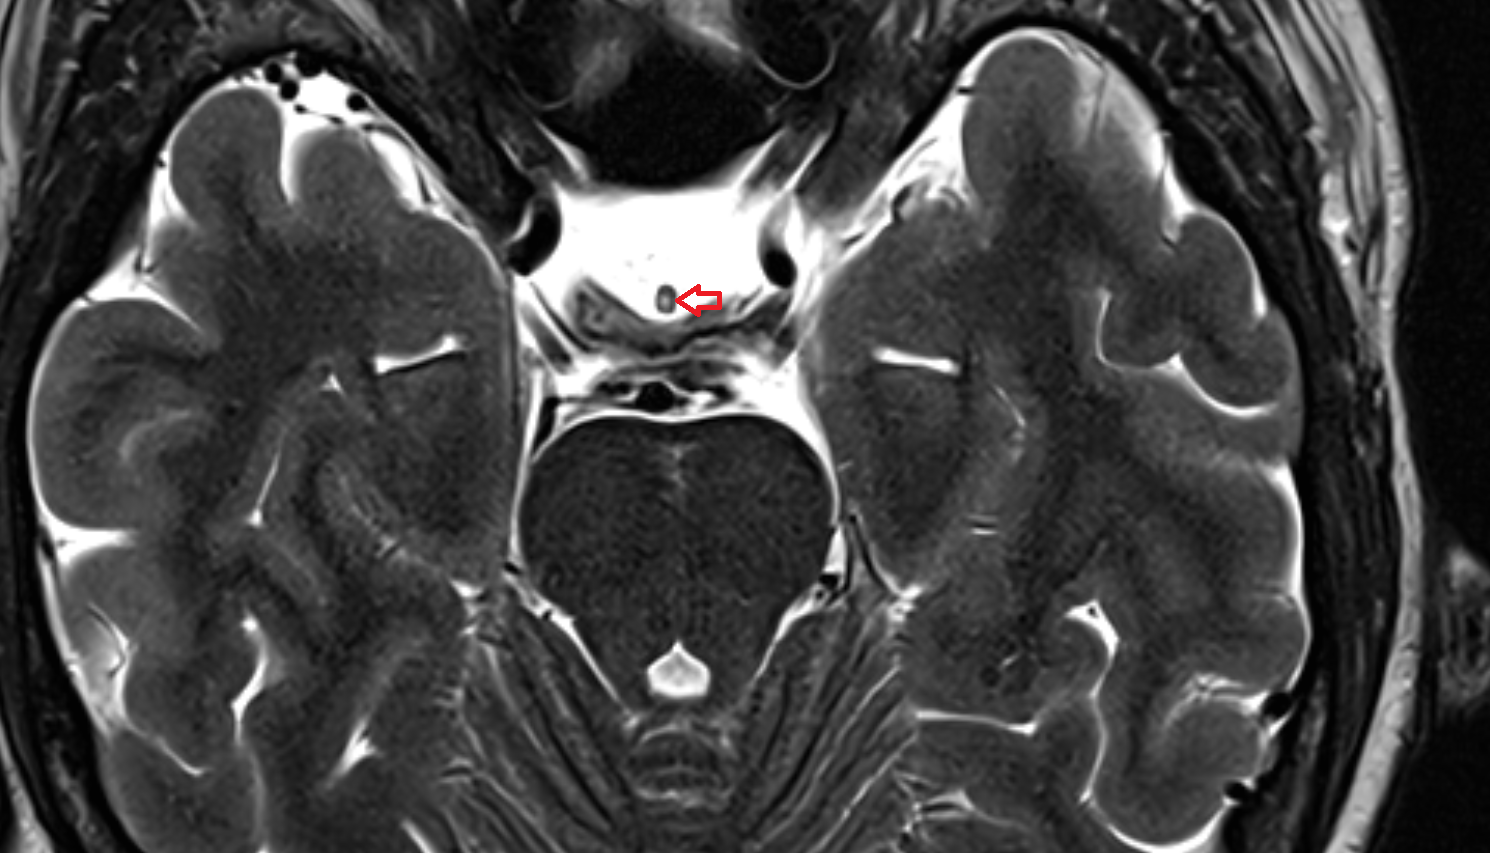

- Abducens nerve (Cranial nerve VI)